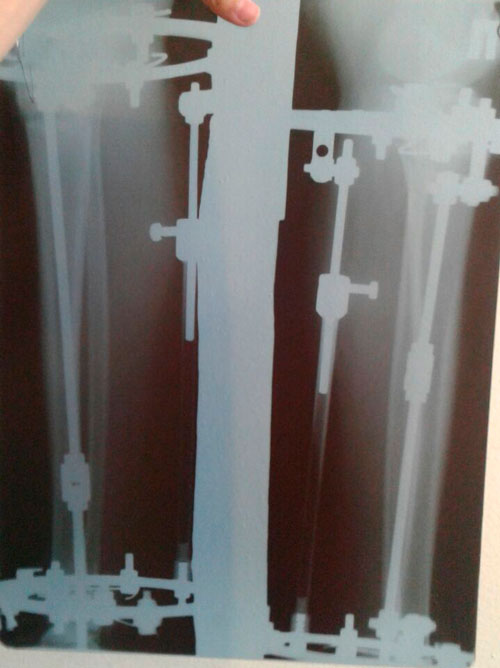

Исходник - 22 года.

Ротация справа под вопросом.

Дата операции 29.03.2016г.